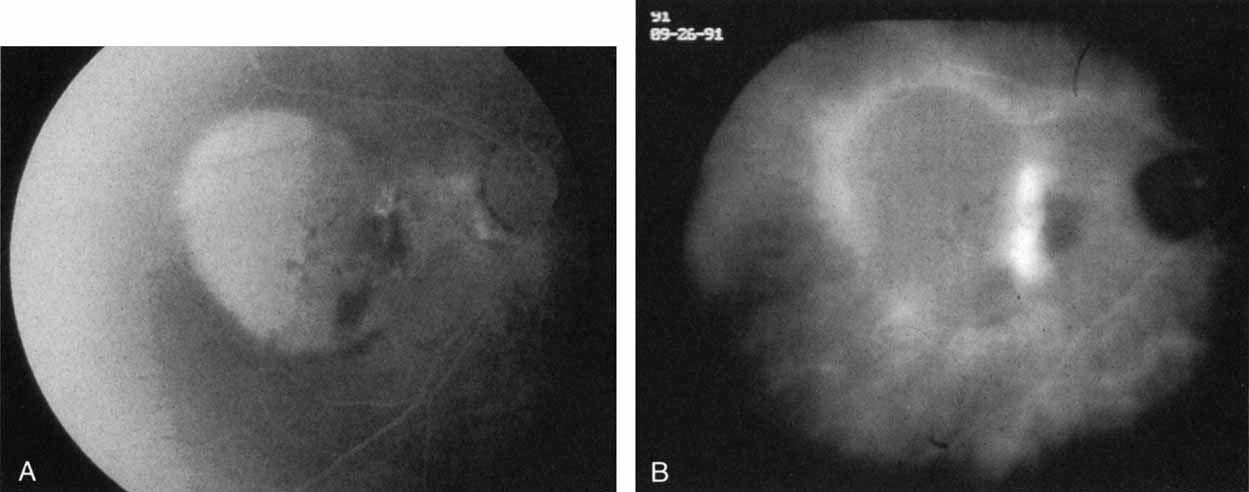

With this clinical diagnostic and histopathologic information available, pilot studies were performed to determine the practicality of using ICG angiographic guidance in the treatment of occult CNV. Slakter and associates28 performed laser photocoagulation treatment on 79 eyes with occult CNV. The occult CNV was successfully eliminated in 57% of patients who underwent ICG-guided treatment (Figs. 5 and 6). The authors found the success rate to be higher (66%) for patients with CNV not associated with PEDs than for those with PEDs (43%). Visual acuity improvement or stabilization was achieved in 57% of all patients. Recurrences were more frequent and more difficult to control in those patients who had associated PEDs on initial clinical presentation. Additional independent studies have reported similar diagnostic and treatment outcomes with the use of ICG angiography in patients with occult CNV.29,30

Sorenson and colleagues31 reported on the diagnostic and therapeutic ability of ICG angiography in patients who had clinical signs of recurrent CNV but who were found to have occult membranes on fluorescein angiography. In a group of 66 patients, 97% were identified as having localized areas of hyperfluorescence on ICG angiography consistent with recurrent CNV (Fig. 7). In laser photocoagulation treatment performed in a subgroup of 29 patients, 62% achieved anatomic resolution and stabilization of the exudative process over time. Visual acuity improved in 66%, 45% of whom achieved a visual acuity of 20/100 or better.